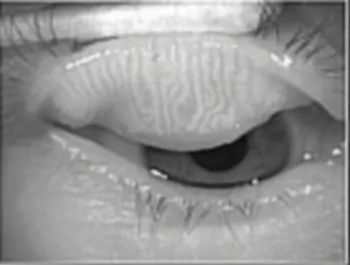

Meibomitis Meibomian Gland disease (MGD)